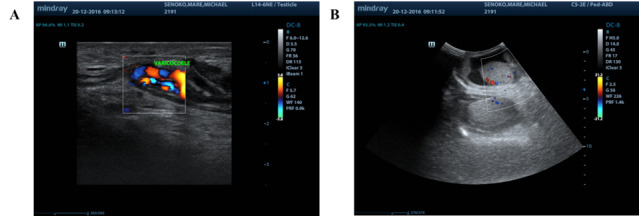

在这个临床案例中,一名男子的优势侧腹股沟受伤,他显然是在前一天的足球训练中受伤的。这名男子无法在无人帮助的情况下行走,只能用轮椅运送。咨询医生在发现很少的临床证据,X光片上也没有任何明显的迹象表明严重急性损伤后,开始怀疑。随后的详细检查显示,肌肉骨骼(MSK)和泌尿生殖道(GUT)系统的肺外结核(EPTB),并伴有病理性髋臼骨折,是腹股沟损伤的原因。EPTB的治疗解决了这种情况,尽管免疫功能低下,但在五年后没有复发,也没有长期后遗症。我们介绍了临床病例和五年的随访。该病例提醒人们,其他情况可能会模仿运动损伤,并进一步说明了这种情况的罕见表现。

In this clinical case, a man presented with a groin injury on his dominant side, which he apparently sustained in football (soccer) practice on the previous day. The man was unable to walk unassisted and had to be transported in a wheelchair. The consulting practitioner grew suspicious upon finding minimal clinical evidence and nothing notable on the X-ray to suggest a severe acute injury. A subsequent detailed workup revealed extrapulmonary tuberculosis (EPTB) of the musculoskeletal (MSK) and genitourinary tract (GUT) systems, complicated by a pathological fracture of the acetabulum, as the cause of the groin injury. Management of the EPTB resolved the condition with no relapse nor long-term sequelae beyond five years, despite being immunocompromised. We present the clinical case and a five year follow-up. The case serves as a reminder of the possibility that other conditions may mimic sports injuries and further illustrates a rare presentation of such a condition.